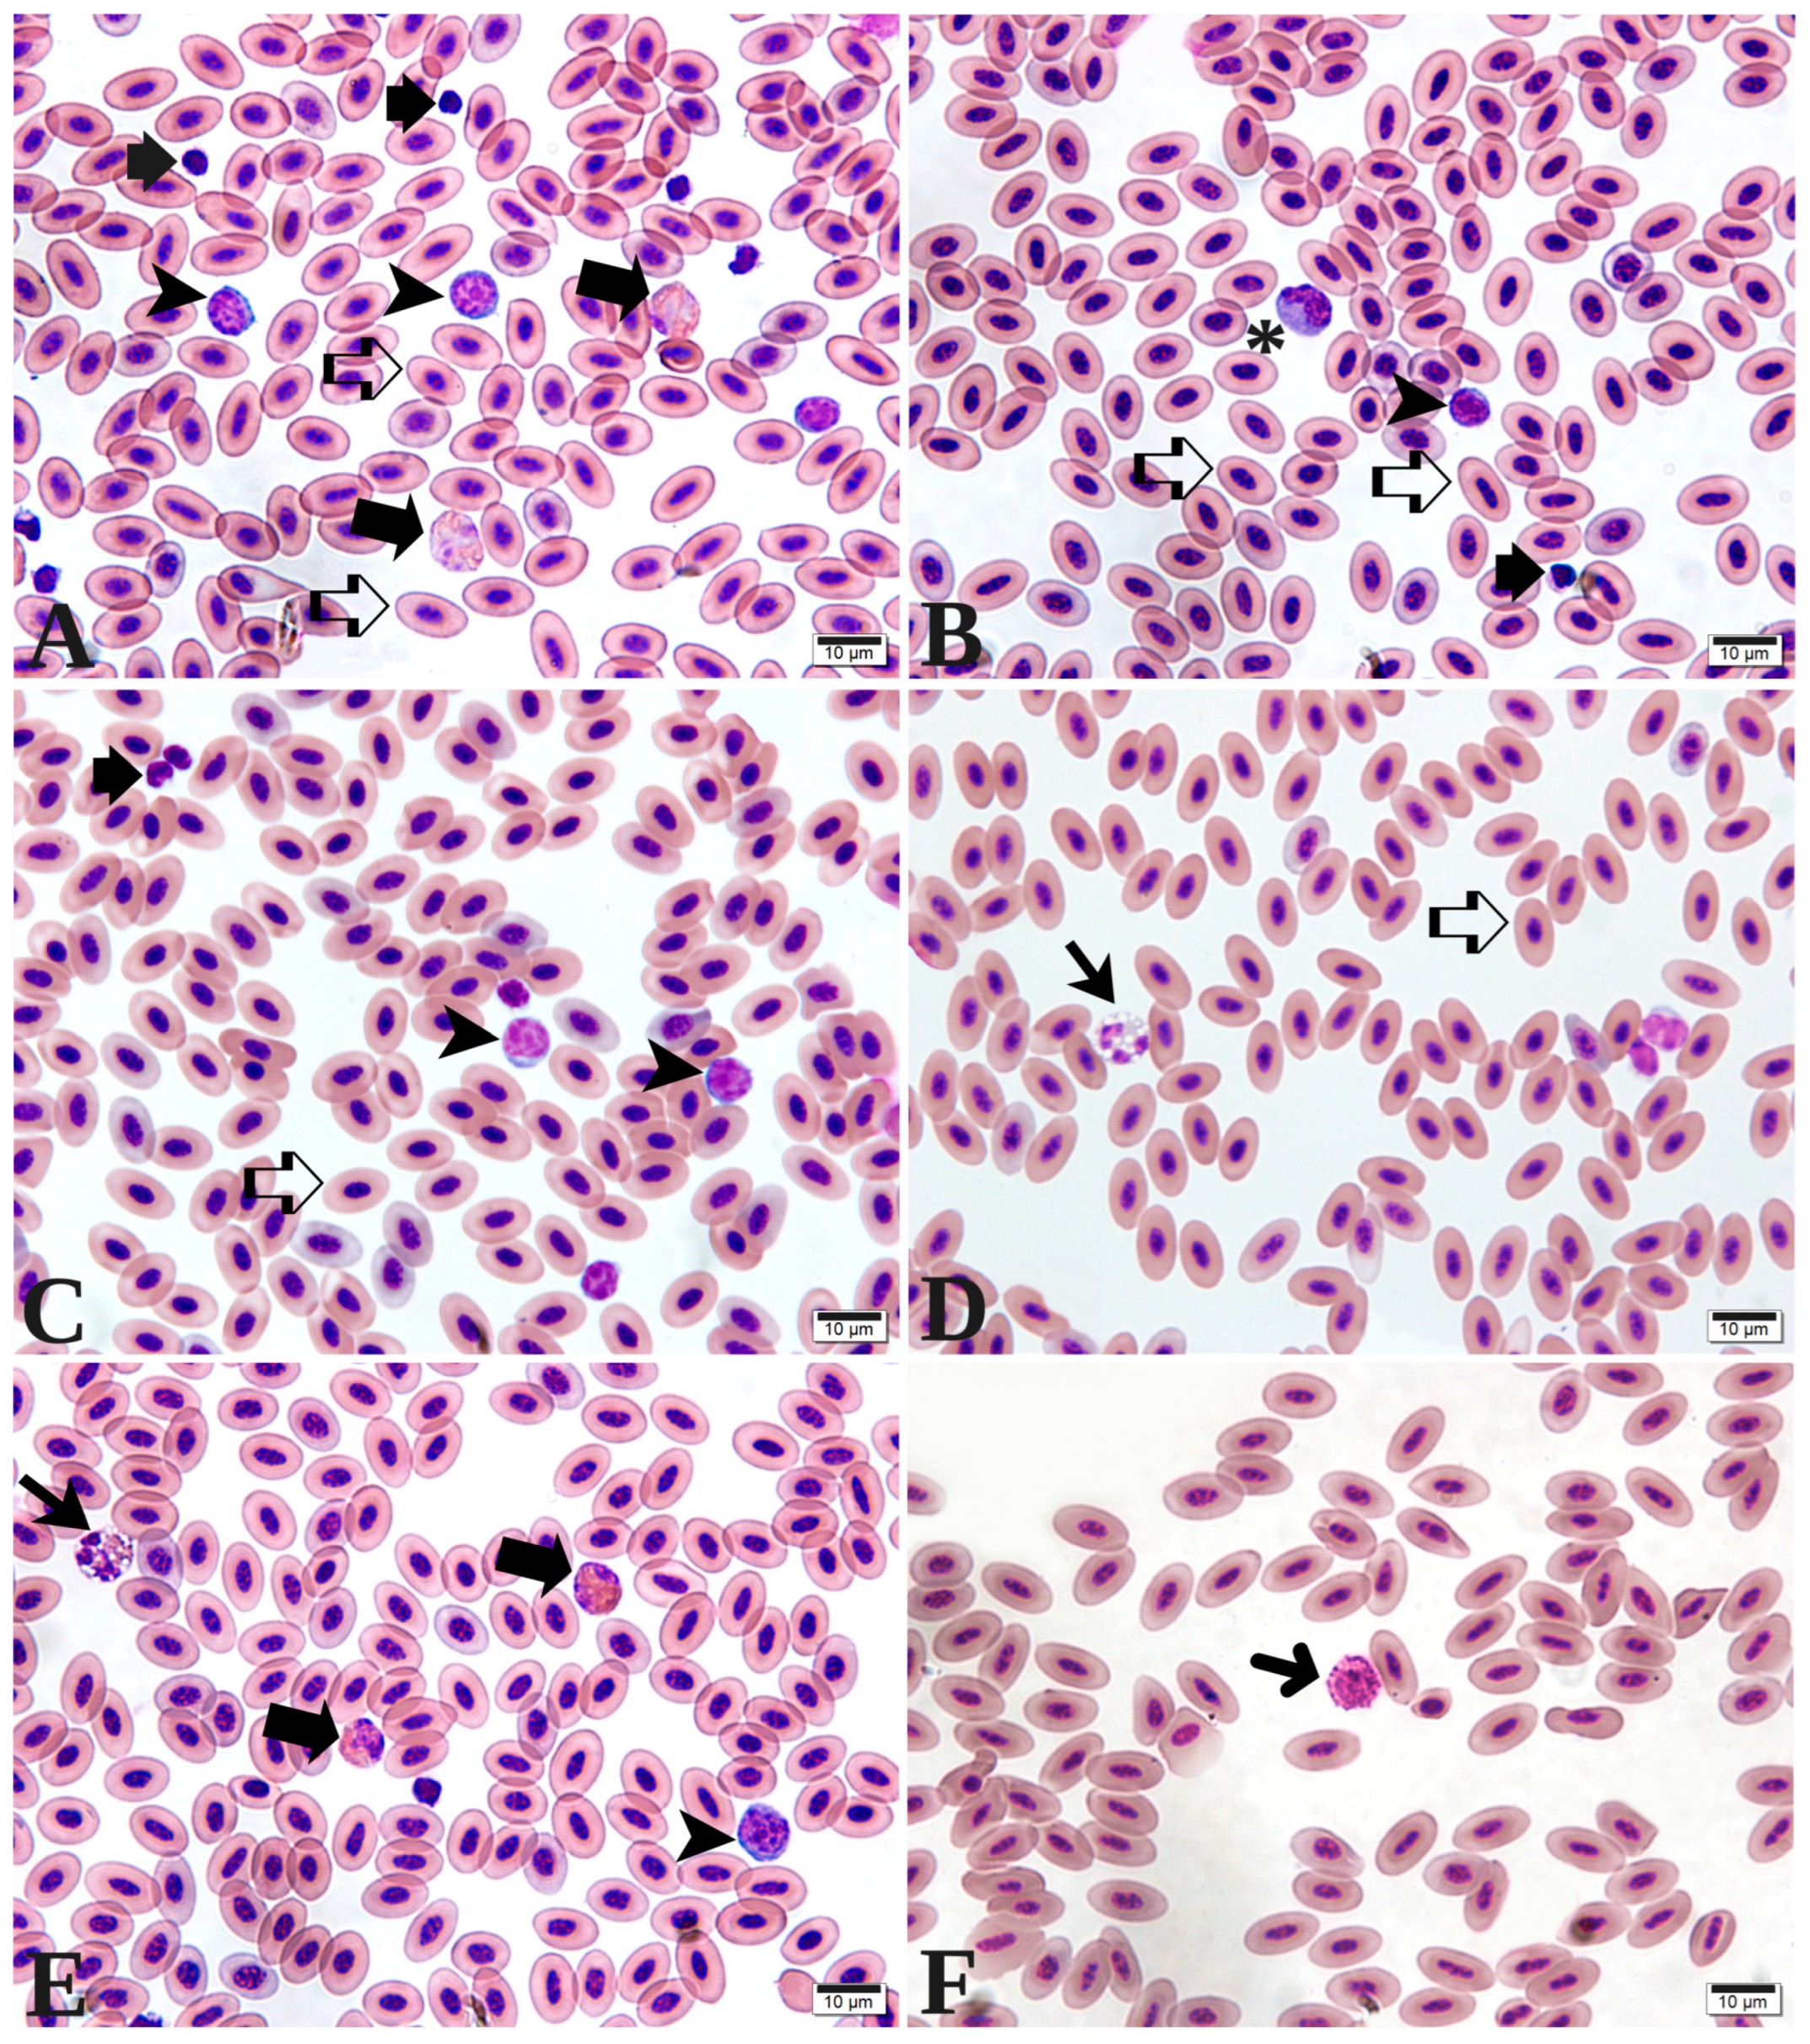

Figure 2. Photomicrographs of blood cells from European quails (Coturnix coturnix coturnix). (A)—Erythrocytes (open arrow), heterophils (thick arrow), thrombocytes (short arrows), and lymphocytes (arrowhead). (B)—Erythrocytes (open arrow), lymphocytes (arrowhead), thrombocytes (short arrows), and monocytes (asterisk). (C)—Erythrocytes (open arrow), thrombocytes (short arrows), and lymphocytes (arrowhead). (D)—Erythrocytes (open arrows) and eosinophils (arrow). (E)—Eosinophils (arrow), heterophils (thick arrow), and lymphocyte (arrowhead). (F)—Basophils (thin arrow). Staining: May–Grünwald–Giemsa. Scale bars: (AF), 10 µm.

Immediately following collection, blood smears were prepared, air-dried, and subsequently stained with May–Grünwald–Giemsa. Packed cell volume (PCV) was determined using the microhematocrit method [24], while hemoglobin concentration was measured in accordance with the methods established by Weiss and Wardrop [25]. Hematimetric indices, following Wintrobe’s methodology, including mean corpuscular volume (MCV) and mean corpuscular hemoglobin concentration (MCHC), were calculated using established mathematical equations [26]. Total erythrocyte, leukocyte, and thrombocyte counts were performed manually in a Neubauer chamber, utilizing blood diluted in 0.01% toluidine blue at a ratio of 1:200 [27]. Differential leukocyte counts, morphological evaluation of blood cells, and screening for hemoparasites were conducted through examination of the blood smear under a light microscope at 1000× magnification. The heterophil-to-lymphocyte ratio (H:L) was determined according to the methodology described by Onbasilar and Aksoy [28]. All analyses were performed at the Veterinary Hospital of the Center for Agricultural Sciences, Federal University of Paraíba.

In relation to the hematological parameters, Table 3 illustrates that during the initial phase (from the 1st to the 14th day of life), no significant interaction between fiber and stimbiotic was detected for any of the analyzed variables. The parameters including packed cell volume, erythrocyte count, mean corpuscular volume (MCV), mean corpuscular hemoglobin concentration (MCHC), and components of the white blood cell series (as depicted in Figure 2)—namely eosinophils, basophils, monocytes, and the heterophil/lymphocyte ratio—demonstrated no statistically significant differences attributable to fiber or stimbiotic inclusion. Conversely, hemoglobin, total leukocyte count, heterophils, and lymphocytes were influenced by the levels of stimbiotic incorporated into the diet. Specifically, hemoglobin levels were elevated in animals receiving stimbiotic, while total leukocyte count, heterophils, and lymphocytes were reduced.

Table 4 presents the hematological values for the growth phase (15 to 35 days of age), revealing no significant interaction between fiber and stimbiotic for any of the hematological variables. However, stimbiotic inclusion significantly enhanced packed cell volume and hemoglobin levels while concurrently decreasing total leukocyte count and lymphocyte counts. With respect to fiber, only eosinophils exhibited significant variation: birds on the control diet presented the lowest eosinophil counts, while those consuming the diet with the highest fiber content (H100) displayed the highest eosinophil values.